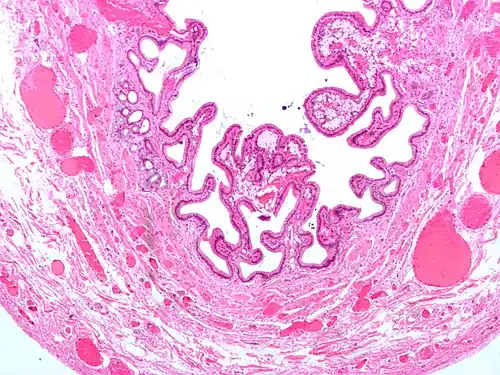

Micrograph of cholesterolosis of the gallbladder

Micrograph of cholesterolosis of the gallbladder -